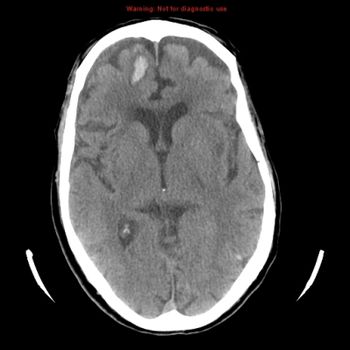

An 85-year-old male patient, medically free, complaining of a fall with trauma to right side of the head, and complaining of heavy tongue and right-sided weakness.